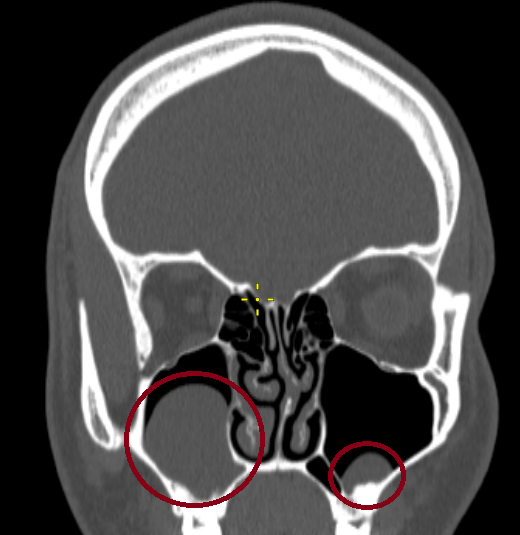

Довольно крупная (на картинке слева) и мелкая (справа) кисты гайморовых пазух на компьютерной томографии (КТ). Удаление в данном случае не требовалось.